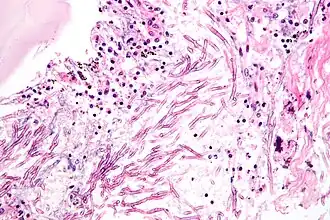

Mycosen of schimmelziekten zijn infecties veroorzaakt door parasitaire schimmels. Ze kunnen zowel bij mensen, dieren als planten voorkomen.

Omdat schimmels heterotrofe organismen zijn, zijn ze afhankelijk van andere organismen voor hun voeding. Mycosen gebruiken het menselijk lichaam voor hun voeding. Ze komen vooral voor op warme en vochtige plaatsen, bijvoorbeeld onder de nagels en op slijmvliezen. Schimmelziekten treden vaak op als de weerstand vermindert, bijvoorbeeld bij suikerziekte.